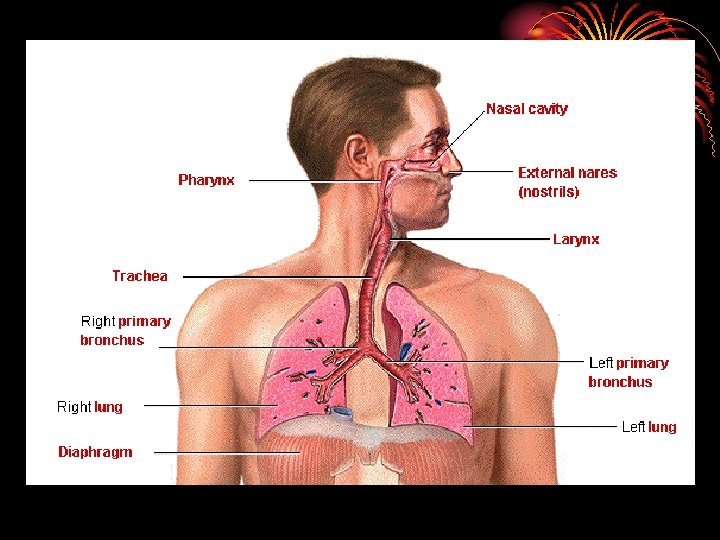

ANATOMY • Right lung three lobes and left two. • Each lobe divided into segments. • Trachea divides into main two bronchi then bronchioles, terminal b. and respiratory b. reaching the alveolar ducts to the alveoli. • Between the trachea and the alveoli airways divide 23 times, 16 conducting & 7 from resp. b. involved in gas exchange.

• area from 2. 5 cm 2 (trachea) to 11800 cm 2 in alveoli ? Air velocity. • 300 million alveoli, 70 m 2. • Alveoli lined by type 1 cells ( flat lining ) and type 11 cells ( granular pneumocytes secrete surfuctant ). • Pleura. • Respiratory muscles.